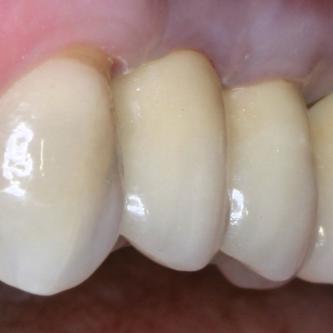

Exemple 2: Un implant remplaçant la racine d'une molaire inférieure gauche.

Exemple 2: La couronne en céramique scellée sur cet implant.